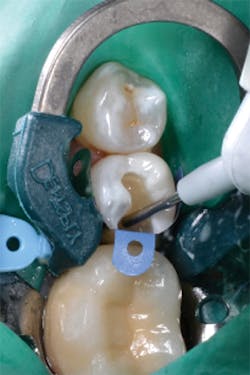

Figure 11: Preoperative view of teeth Nos. 4 and 5. The treatment plan includes composite restorations.

Figure 12: Final preparations on teeth Nos. 4 and 5. The Palodent Plus Sectional Matrix System has been used to isolate the MOD prep on tooth No. 4 and MO prep on tooth No. 5. The Palodent Plus Sectional Matrix System can be configured to restore multiple surfaces and multiple teeth in the same quadrant.